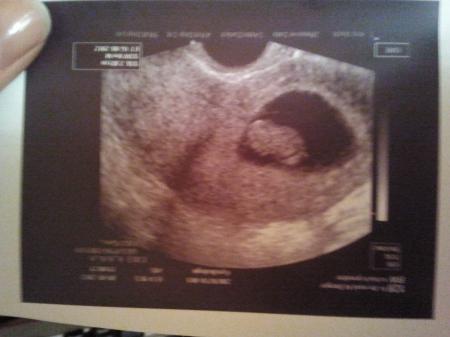

Ich hab seit ein Paar Tagen immer wieder Bauchkrämpfe mit extremem Schwindel .... deshalb bin ich gerade zum Frauenarzt gegangen ... eig hatte ich mir vorgenommen nicht so ängstlich zu sein aber dann bin ich doch hin gegangen und wieder Sorgenfrei zu sein .... Na ja meine Frauenärztin war leicht genervt und deshalb habe ich kaum etwas gefragt oder gesagt ... Sie hat 1 Min Ultraschall gemacht und schnell ein Bild ausgedruckt ... Das Herzchen schlägt zum Glück und sie meinte ich soll mir keine Sorgen machen und es ist alles ok .... Nur warum hat sich mein Krümmel weder Heute noch vor 1 Woche auf dem Ultraschall bewegt ... ich habe so gehofft das es irgendeine Bewegung zeigt ... So viele von euch schreiben das ihr so begeistert seit weil eure Krümmel Purzelbäume machen und boxen ... ist es normal das es sich nicht bewegt ??? und findet ihr die Größe von 2 cm normal für die 10 Woche ??? Ich mache mir so Sorgen weil die ertsen Wochen alles andere waren als einen leichten Start ... ich hoffe ich nerve euch nicht , nur eine Frage habe ich noch : stehen auf euren Ultraschallbildern immer ganu andere Ssw und Tage als das was diue Frauenärztin euch sagt .... also zum Beispiel bin ich heute 9+2 und auf dem US steht 8+4.... Ich Danke euch jetzt schon mal für eure Antworten .. Lg Jenny

das ist das binden von heute.

Bild zu